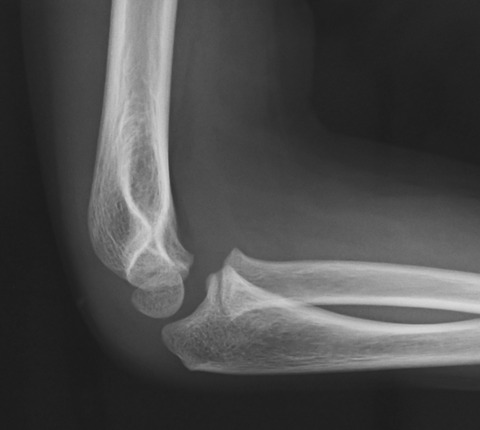

先日、小児の上腕骨外顆骨折の手術がありました。

上腕骨外顆骨折は、小児の骨折の中でも難易度の高い手術のひとつです。

手術が上手いくか否かは、手術前の段階から始まっています。一般的に肘周囲骨折では軟部組織が高度に腫脹します。このため、至適位置に皮膚切開を加えることが難しいです。

上図は正常例の肘関節側面像ですが、上腕骨顆部の肘頭窩部(8の字の中心部)を透視下にマーキングします。こうすることで正確な側面から骨折部にアプローチすることが可能となります。

通常、上腕骨外顆骨片は伸筋群に牽引されるので掌外側に転位しますす。このため、外顆骨片を触知して、その直上に皮膚切開を加えると前方過ぎることが多いのです。

小児の肘関節はとても小さいので、皮膚切開の位置がイマイチだと術中操作で苦労します。このため、手術を始める前からスムーズに終了するための闘いが始まっているのです。